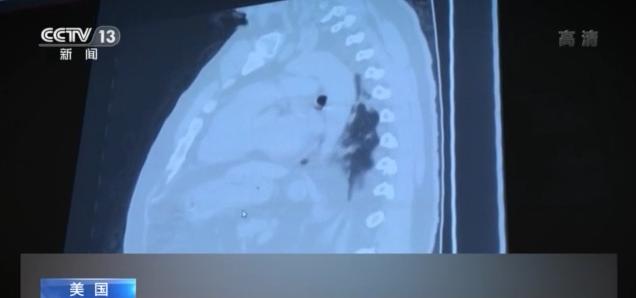

美国新冠肺炎疫情的失控让各地的医院承受着前所未有的巨大压力,医护人员长期处于高负荷工作状态。美国有线电视新闻网的记者日前再次对6月份曾经探访过的医院——休斯敦联合纪念医疗中心——进行了回访,那里的医生和护士坦言,休斯敦乃至得克萨斯州的疫情越来越严重,他们看到了太多的死亡。

今年6月,由于新冠肺炎住院患者太多,得克萨斯州休斯敦联合纪念医疗中心将两个普通病区改造为新冠肺炎隔离病区,而现在,由于患者人数激增,医院不得不再增加一个隔离病区。